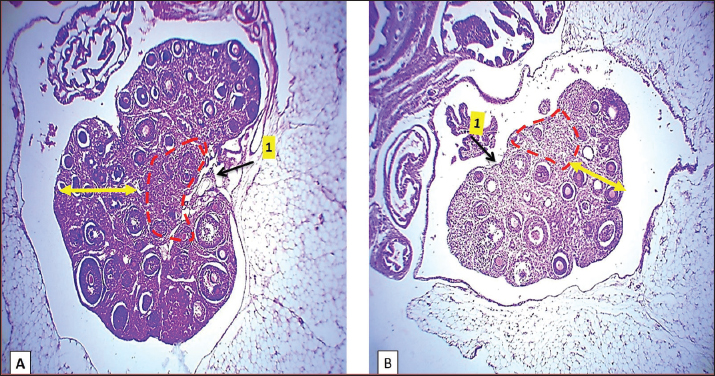

Fig. 2. Microphotograph showing the microscopic structure of the ovary in 2 weeks age group, the left ovary (A), the right ovary (B), the medulla (dashed circle), the cortex (arrows), and the ovarian hilum (1). H&E 40X.

Histologically: The ovaries were covered with simple cuboidal epithelium, and the ovarian cells overlain fibrous connective tissue, tunica albuginea. The parenchyma was composed of two zones, the outer cortex and inner medulla, with the shallow notch representing the primary ovarian hilum. Within the cortex, there were clusters of oocytes (Fig. 2) and numerous primordial, primary, secondary, and degenerative follicles (Fig. 3); the ovaries at this age are devoid (absant) of mature follicles (Graafian follicle) and the corpus luteum. The ovarian medulla was clear and easily recognized at this age, and it comprised connective tissue with prominent blood vessels (Fig. 4).

The microscopic measurements showed that the numbers of primordial, primary, and secondary follicles were higher in the right ovary than in the left ovary, and the diameters of these follicles were significantly higher in the right ovary than in the left, at a significant level of p ≤ 0.01 (Tables 2 and 3). The immunohistochemical observations showed that T lymphocytes were scarce and distributed in the ovarian parenchyma and around the follicles (Fig. 5).